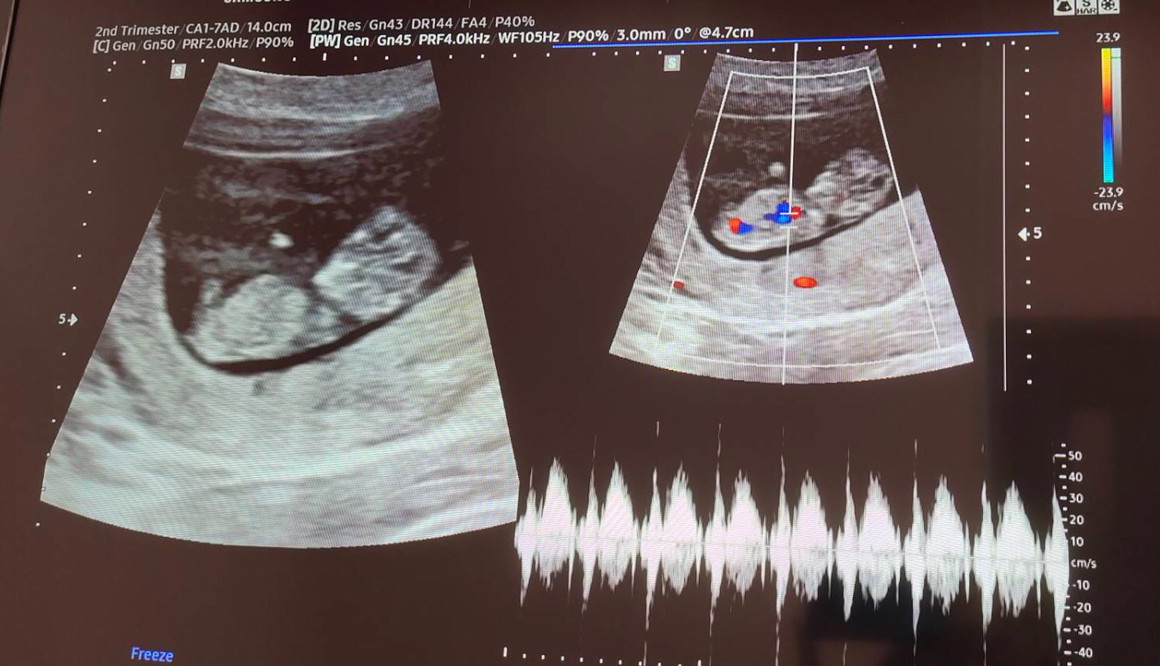

11 สัปดาห์ ซาวด์มาเจอลูกแบบนี้ถือว่าเขาตัวใหญ่ไหมคะหรือปกติ

ปกติจ้า เท่าๆบ้านนี้